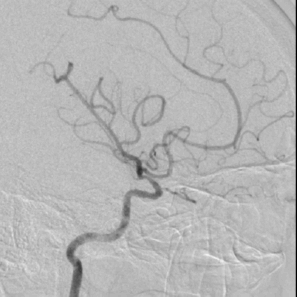

5、 术后正侧位造影及3D造影

多角度投照显示支架帖壁良好,远端血管显影好,前向血流mTICI3级。